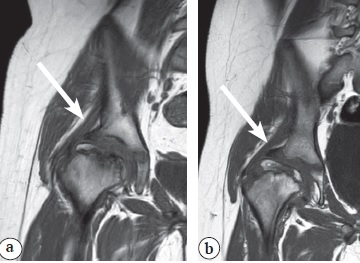

По результатам проведенного МРТ-исследования, помимо подтверждения деформации хрящевой модели головки бедренной кости, нами было обнаружено, что у пациентов со значениями углов Sharp и Tönnis, находящихся в пределах среднефизиологической вариации, отмечалось горизонтальное положение labrum acetabuli, а у пациентов со значениями углов Sharp и Tönnis, превышающими верхнюю границу среднефизиологической вариации, отмечалось обратное вертикальное положение labrum acetabuli (рис. 4).

Рис. 4. МР-картина положения labrum acetabuli (отмечена стрелкой) у пациентов: a — значения углов Sharp и Tönnis находятся в пределах среднефизиологической вариации (горизонтальное положение); b — значения углов Sharp и Tönnis превышают верхнюю границу среднефизиологической вариации (обратное вертикальное положение)

Figure 4. MR image of the acetabular rim position (marked with an arrow) in patients: a — values of Sharp and Tönnis angles are within the average physiological variation (a horizontal position); b — values of Sharp and Tönnis angles exceed the upper limit of the average physiological variation (a reverse vertical position)